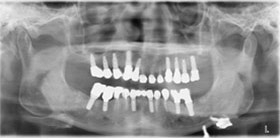

治療前X光片,多處缺牙及嚴重牙周破壞。

病患最終X光片。